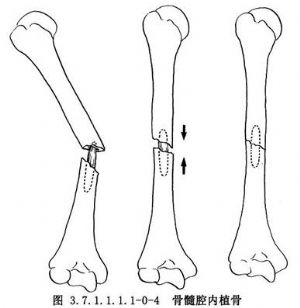

皮質骨剝離術系Judet所倡導,其方法是切口直達骨質,在骨膜下鑿去薄層骨片,但必須保持骨片與周圍軟組織的血運聯繫。皮質骨剝離範圍佔骨周徑1/2~2/3(圖3.7.1.1.1.1-0-1)。兩骨折端均須做皮質骨剝離,並使骨與其外覆蓋的軟組織之間形成袋狀,以便同時做骨折端周圍植骨(phemister bone graft)(圖3.7.1.1.1.1-0-2)。但在對位對線較好,纖維瘢痕可維持骨折端穩定時,通常是將細條形松質骨置於骨折端瘢痕周圍。對切除整新骨端而形成斷端間隙或缺損者,須用松質骨嵌入移植,以免喪失肢體長度。滑行植骨(sliding bone graft)亦稱倒置植骨,方法是在骨折端兩側切取不等長的長方形骨條,其寬度不超過骨幹周徑的1/3。將條狀骨倒置,使較長的骨塊騎跨骨折端兩側(圖3.7.1.1.1.1-0-3)。髓腔內植骨(medullary bone graft)(圖3.7.1.1.1.1-0-4)是用一側帶皮質的柱狀骨塊插入骨折端兩側髓腔內,有加強固定穩定性和促進成骨的雙重效果。長骨幹不愈合骨折用單純植骨術治療的適應證很少,一般都需同時使用堅固的內固定或外固定,爲骨癒合提供生物學和力學兩方麪條件。